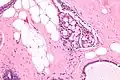

| Micrograph of collagenous spherulosis with the characteristic histomorphology - intratubular eosinophilic material with a spoke-like arrangement. H&E stain. | |

Collagenous spherulosis is characterized by a tubular/cribriform architecture with intratubular eosinophilic material that classically is arranged like the spokes of a wheel ("radial spikes"). There is usually no mitotic activity, and two cells populations (epithelial & myoepithelial) are present, like in benign breast glands.

The lesions are typically small (less than 50 spherules per lesion, less than 100 micrometers in size) and may be multifocal.